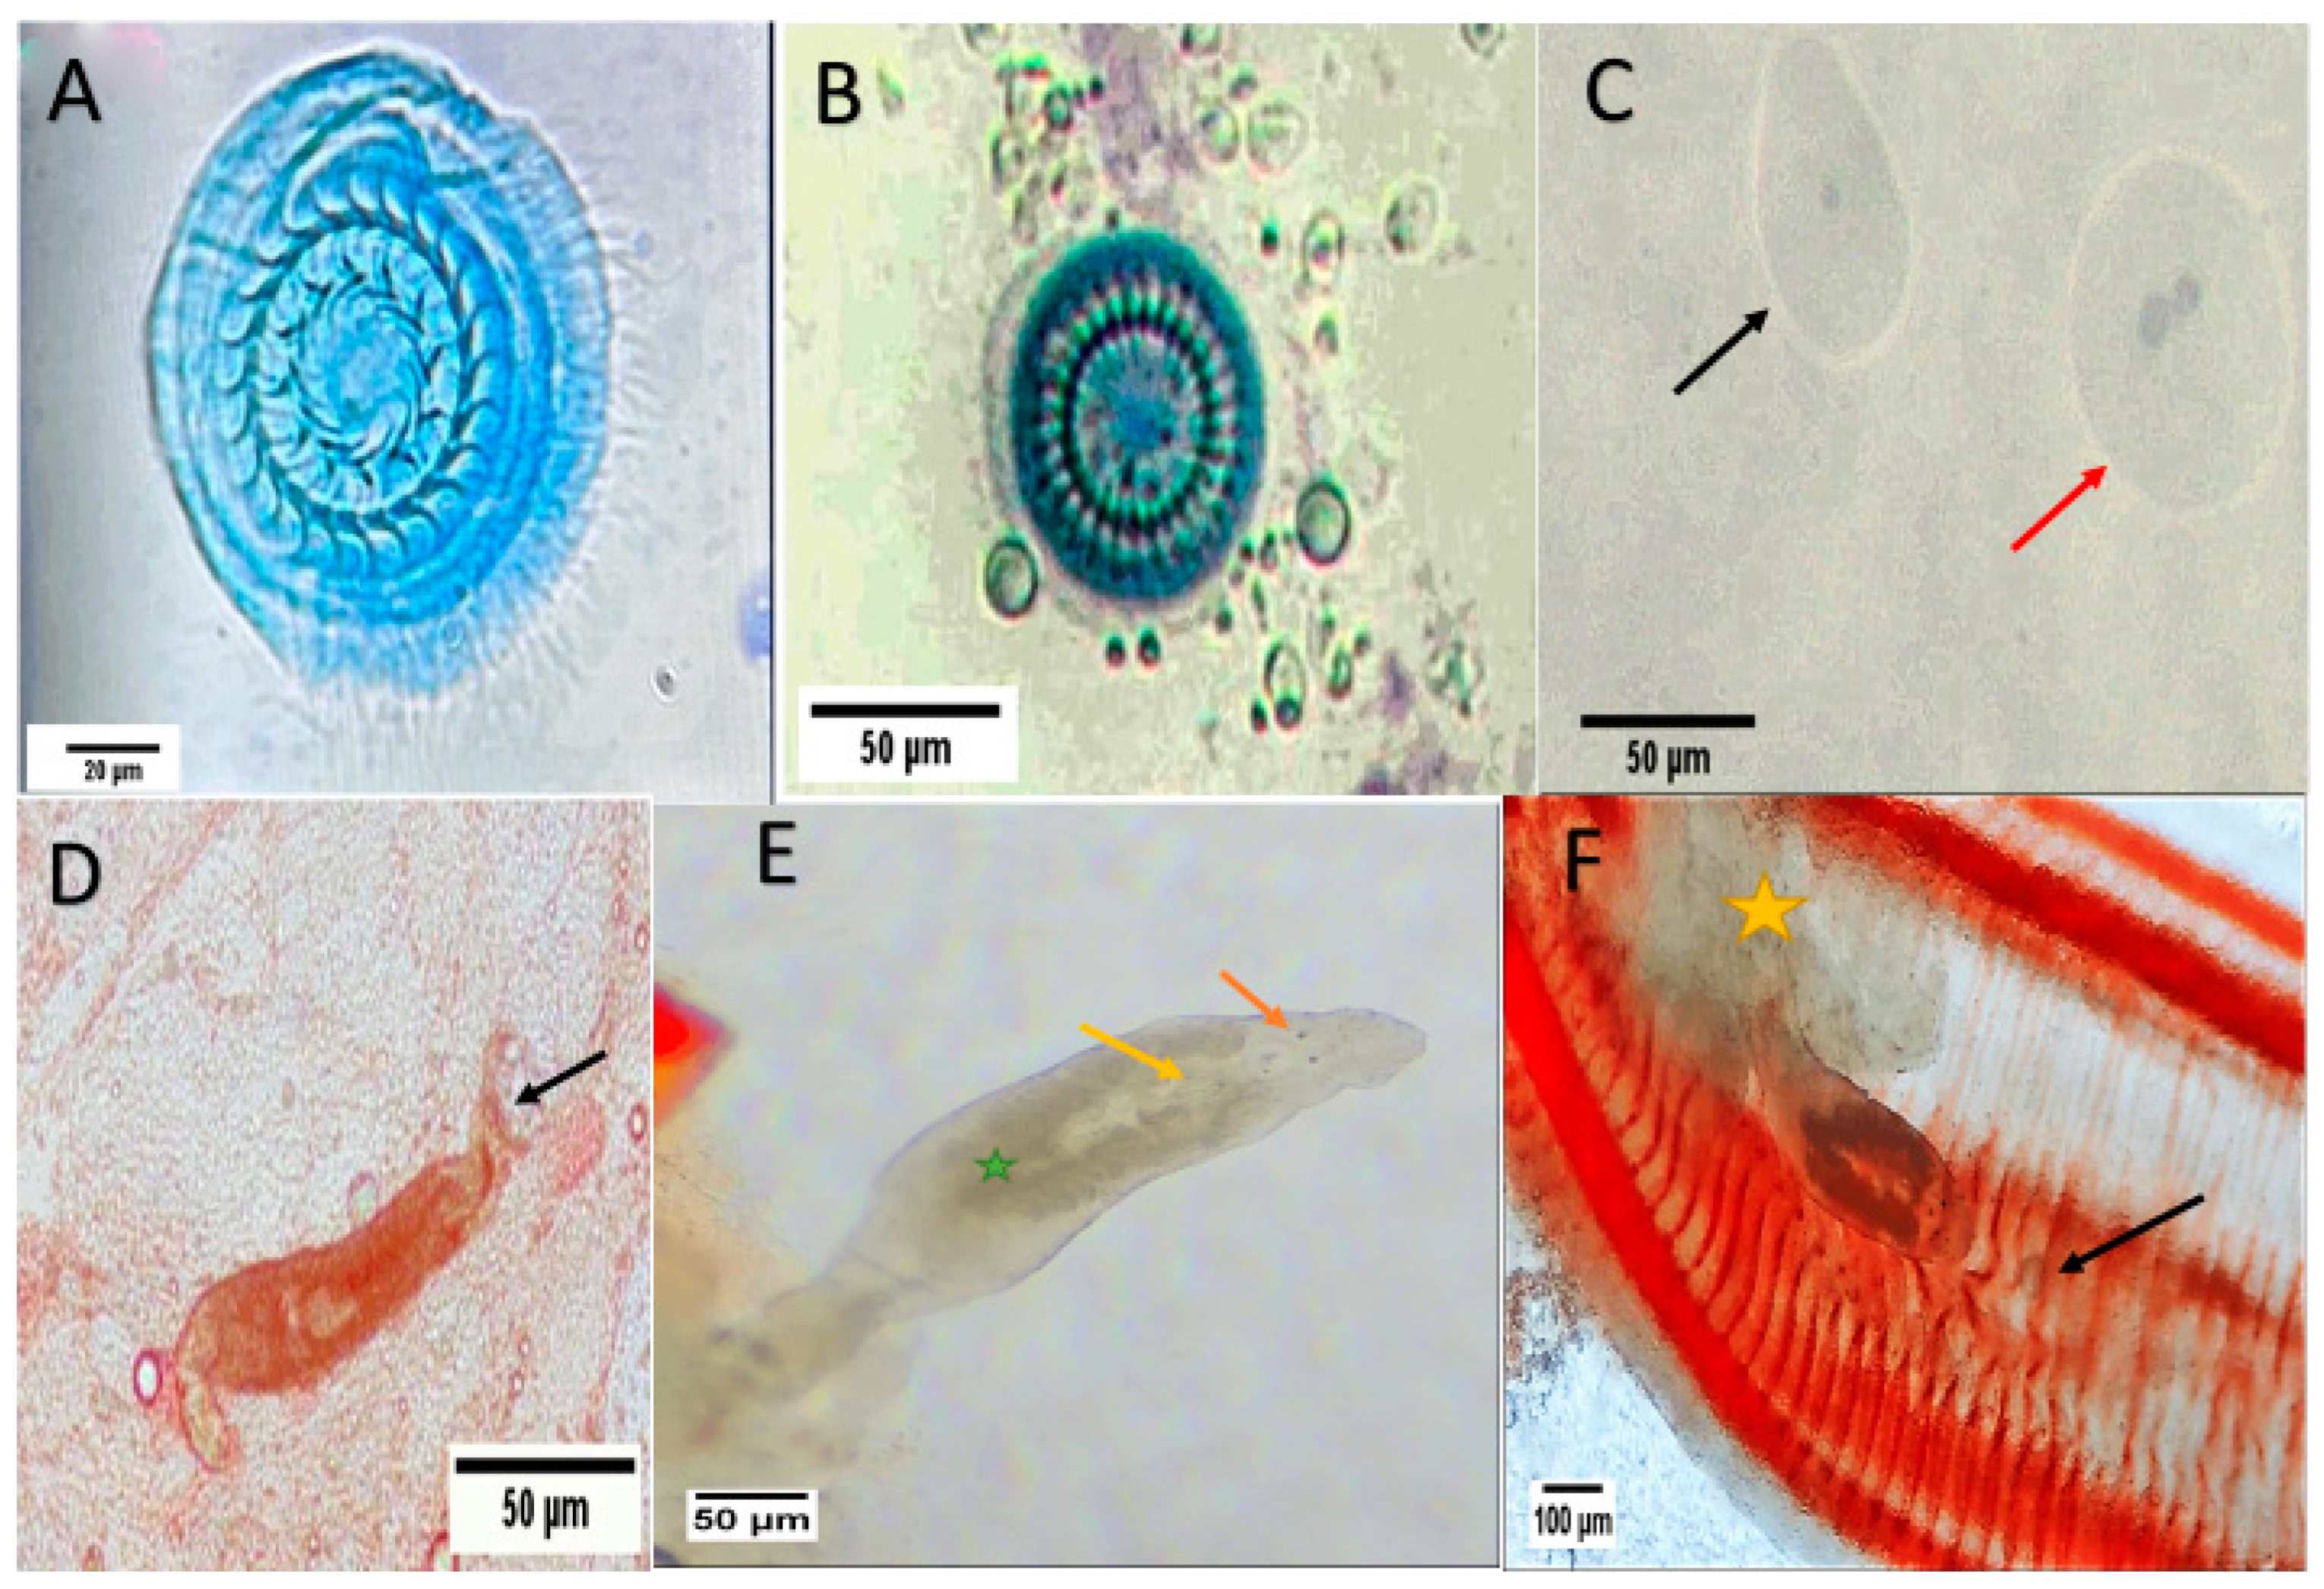

3.2. Fish Parasites Assemblage

3.3. Haematological and Biochemical Analysis